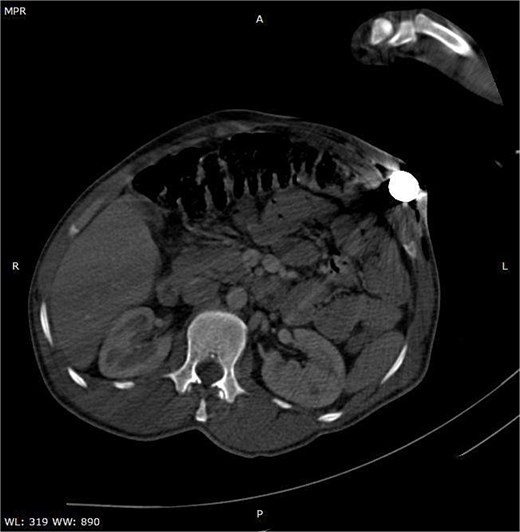

A CT scan of the pelvis, abdomen, and chest revealed the metal rod’s trajectory, penetrating the medial aspect of the left proximal thigh and traversing the left inguinal region lateral to the femoral vessels and nerve, with no evidence of vascular injury or hematoma (Figs 2 and 3). The rod continued through the abdominal wall in the subcutaneous plane without entering the peritoneal cavity, and no free fluid was detected (Fig. 4). It then extended through the left chest wall, associated with subcutaneous emphysema, but no intrathoracic injury was evident.

Axial CT image illustrating the entry site of the metallic rod through the abdominal wall.